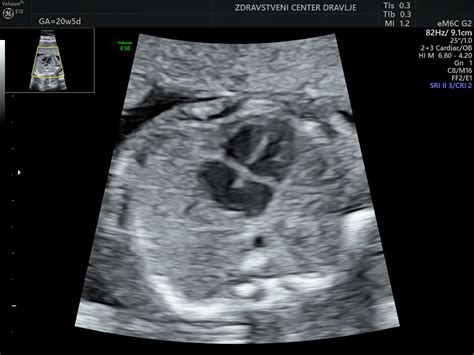

Nuhalna svetlina je neinvaziven presejalni test, ki temelji na ultrazvočni meritvi debeline tekočine za tilnikom ploda. Povečana debelina nuhalne svetline lahko nakazuje na povečano tveganje za kromosomske nepravilnosti, vendar sama po sebi ni dokončna diagnoza. Za natančnejšo potrditev ali ovržbo suma se uporabljajo nadaljnje preiskave, kot sta invazivni test (amniocenteza ali horionska biopsija) ali neinvazivni krvni test (NIPT).

Eno izmed ključnih vprašanj, ki se pojavlja v mnenjih, je kakovost ultrazvočne opreme. Medtem ko so nekatere nosečnice izrazile zadovoljstvo z aparati in so videle "ful dobro", drugi menijo, da so bili aparati zastareli. Vendar pa je v novejših informacijah omenjeno, da je Diagnostični center Strah pridobil novo ultrazvočno opremo, "Acuson S 2000 Siemens", ki predstavlja "v svetovnem merilu enega najbolj kakovostnih ultrazvokov". To nakazuje na morebitno izboljšanje kakovosti slik in diagnostičnih možnosti v primerjavi s starejšimi izkušnjami.

Poleg nuhalne svetline dr. Strah izvaja tudi morfologijo in druge ginekološke preglede. Nekatera mnenja nakazujejo, da je dr. Strah zelo vešča v odkrivanju zgodnjih znakov za Downov sindrom in drugih anomalij, kar je posledica njenega rednega izobraževanja na priznanih mednarodnih centrih, kot je Fetal Medicine Foundation v Londonu.